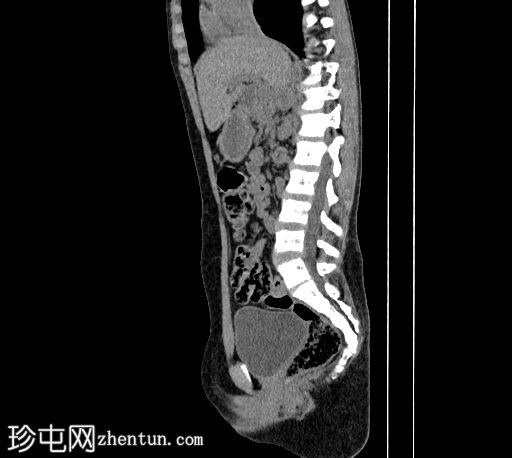

矢状位

平扫

胰体和胰尾未显影,仅胰头显影,可能为背侧胰腺发育不全所致。

肠袢聚集于右侧肋下区,提示肠旋转不良。

左肾体积较小,肾实质相对扭曲,呈分叶状,可见少量肾实质囊肿。左肾上盏轻度突出。

右肾发育不全。

疑似肾下段下腔静脉(IVC)缺如。